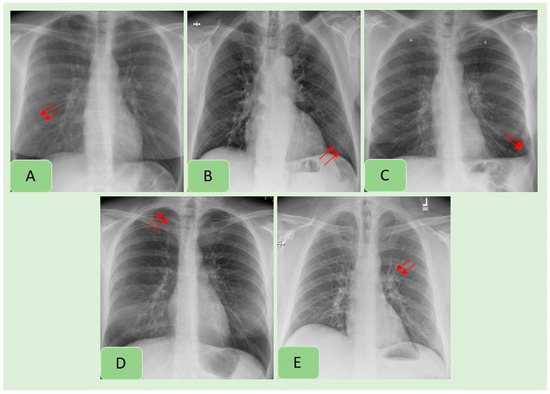

Figure 4. Examples of CXR findings missed by both the AI algorithm and in the original radiology reports: pulmonary nodule (A), consolidation (B), pleural effusion (C), pneumothorax (D) and hilar prominence (E).

Table 3 summarizes country-wise distribution of CXR findings at the vendor-recommended thresholds. There were variations in the performance of the algorithm across the Indian and US sites, although the differences were not statistically significant (p > 0.2). Pneumothorax and mediastinal widening had the lowest AUCs for the AI algorithm, whereas highest AUCs were reported for pleural effusions, enlarged cardiac silhouette, hilar prominence and rib fractures. Figure 2 presents examples of the AI-detected CXR findings which were not reported in the radiology reports. Figure 4 presents findings missed by both the AI algorithm and in the original radiology reports.